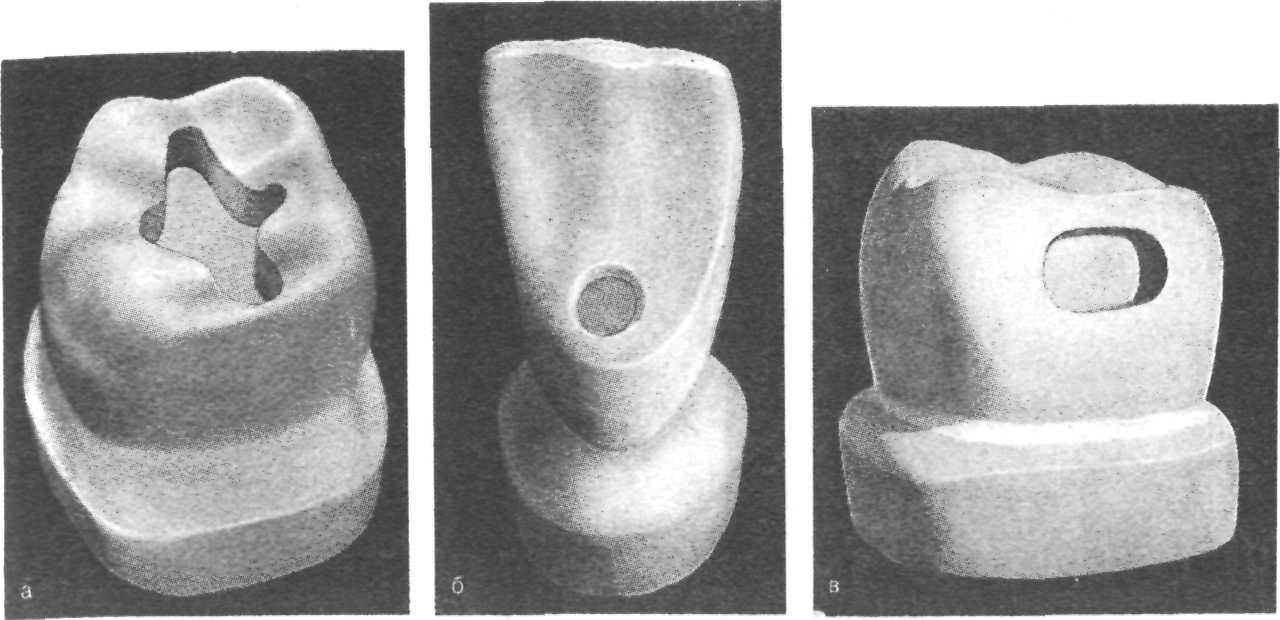

Препарирование кариозных полостей III класса: пошаговое руководство с фото